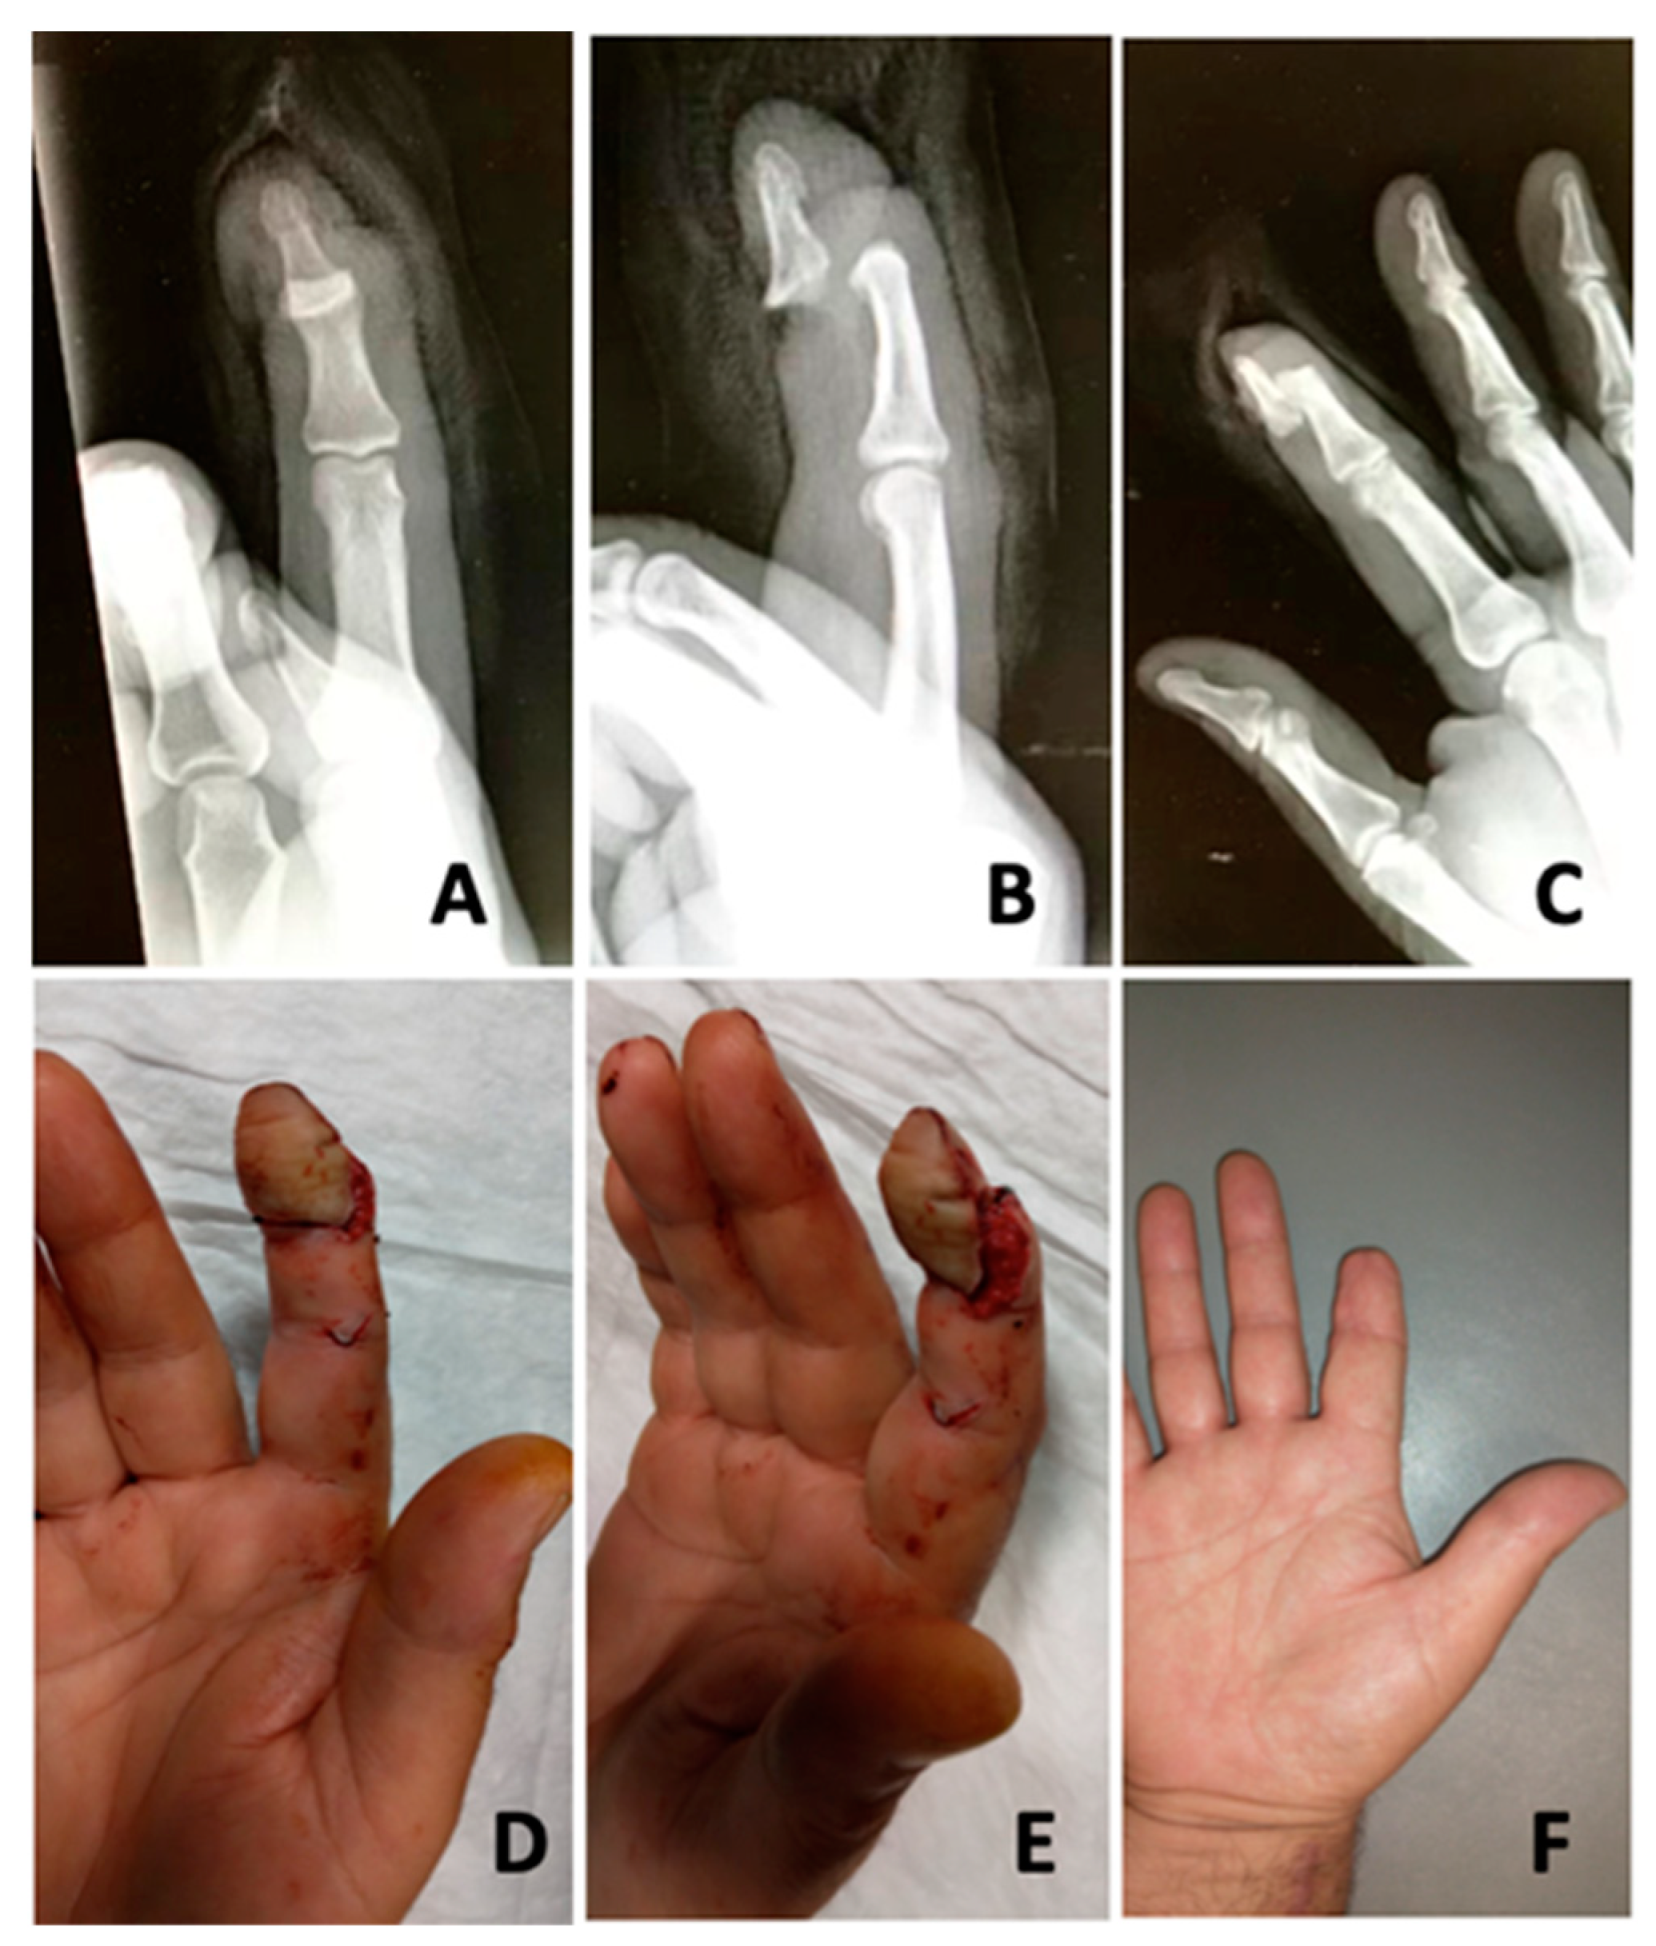

Figure 2. Avulsion injury of the distal phalanx of the second finger. (A,B) Volar and lateral views of the tissue continuity shown only by the flexor tendon. (CE) Frontal, oblique and lateral radiographs showing complete volar dislocation of the distal phalanx without fracture. (F) Final aspect after reduction.